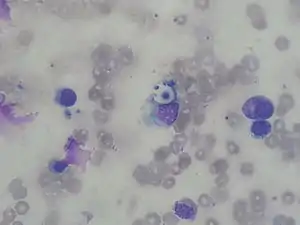

Biopsy

A special stain may be needed to see the cryptococcus capsule.[33]

.jpg.webp) Mucicarmine stain: bright pink cryptococcosis capsule[33]

Mucicarmine stain: bright pink cryptococcosis capsule[33] Field stain: thick cryptococcosis capsule

Field stain: thick cryptococcosis capsule_histiocytic_penumonia.jpg.webp) H&E stain: histiocytic penumonia

H&E stain: histiocytic penumonia_Alcian_blue-PAS.jpg.webp)